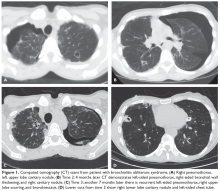

The patient is diagnosed with BOS and is treated for several months with prednisone 40 mg/day weaned over 3 months. She is started on inhaled corticosteroids, a proton pump inhibitor, and azithromycin 3 times per week, but she has a progressive decline in FEV1. She starts pulmonary rehabilitation but continues to functionally decline. Over the next year she develops bilateral pneumothoraces and bilateral cavitary nodules (Figure 1).

Spontaneous air leak syndrome has been described in a little more than 1% of patients undergoing HSCT and has included pneumothorax and mediastinal and subcutaneous emphysema.46 It appears that air leak syndrome is more likely to occur in patients with chronic GVHD.47 The association between chronic GVHD and air leak syndrome could explain this patient’s recurrent pneumothoraces. The recurrent cavitary nodules are suspicious for infectious etiologies such as nontuberculous mycobacteria, tuberculosis, and fungal infections.